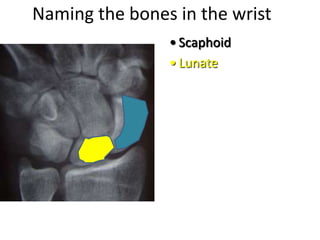

This document provides an overview of hand anatomy including:

- Naming the bones, joints, tendons, nerves and skin landmarks of the hand and wrist.